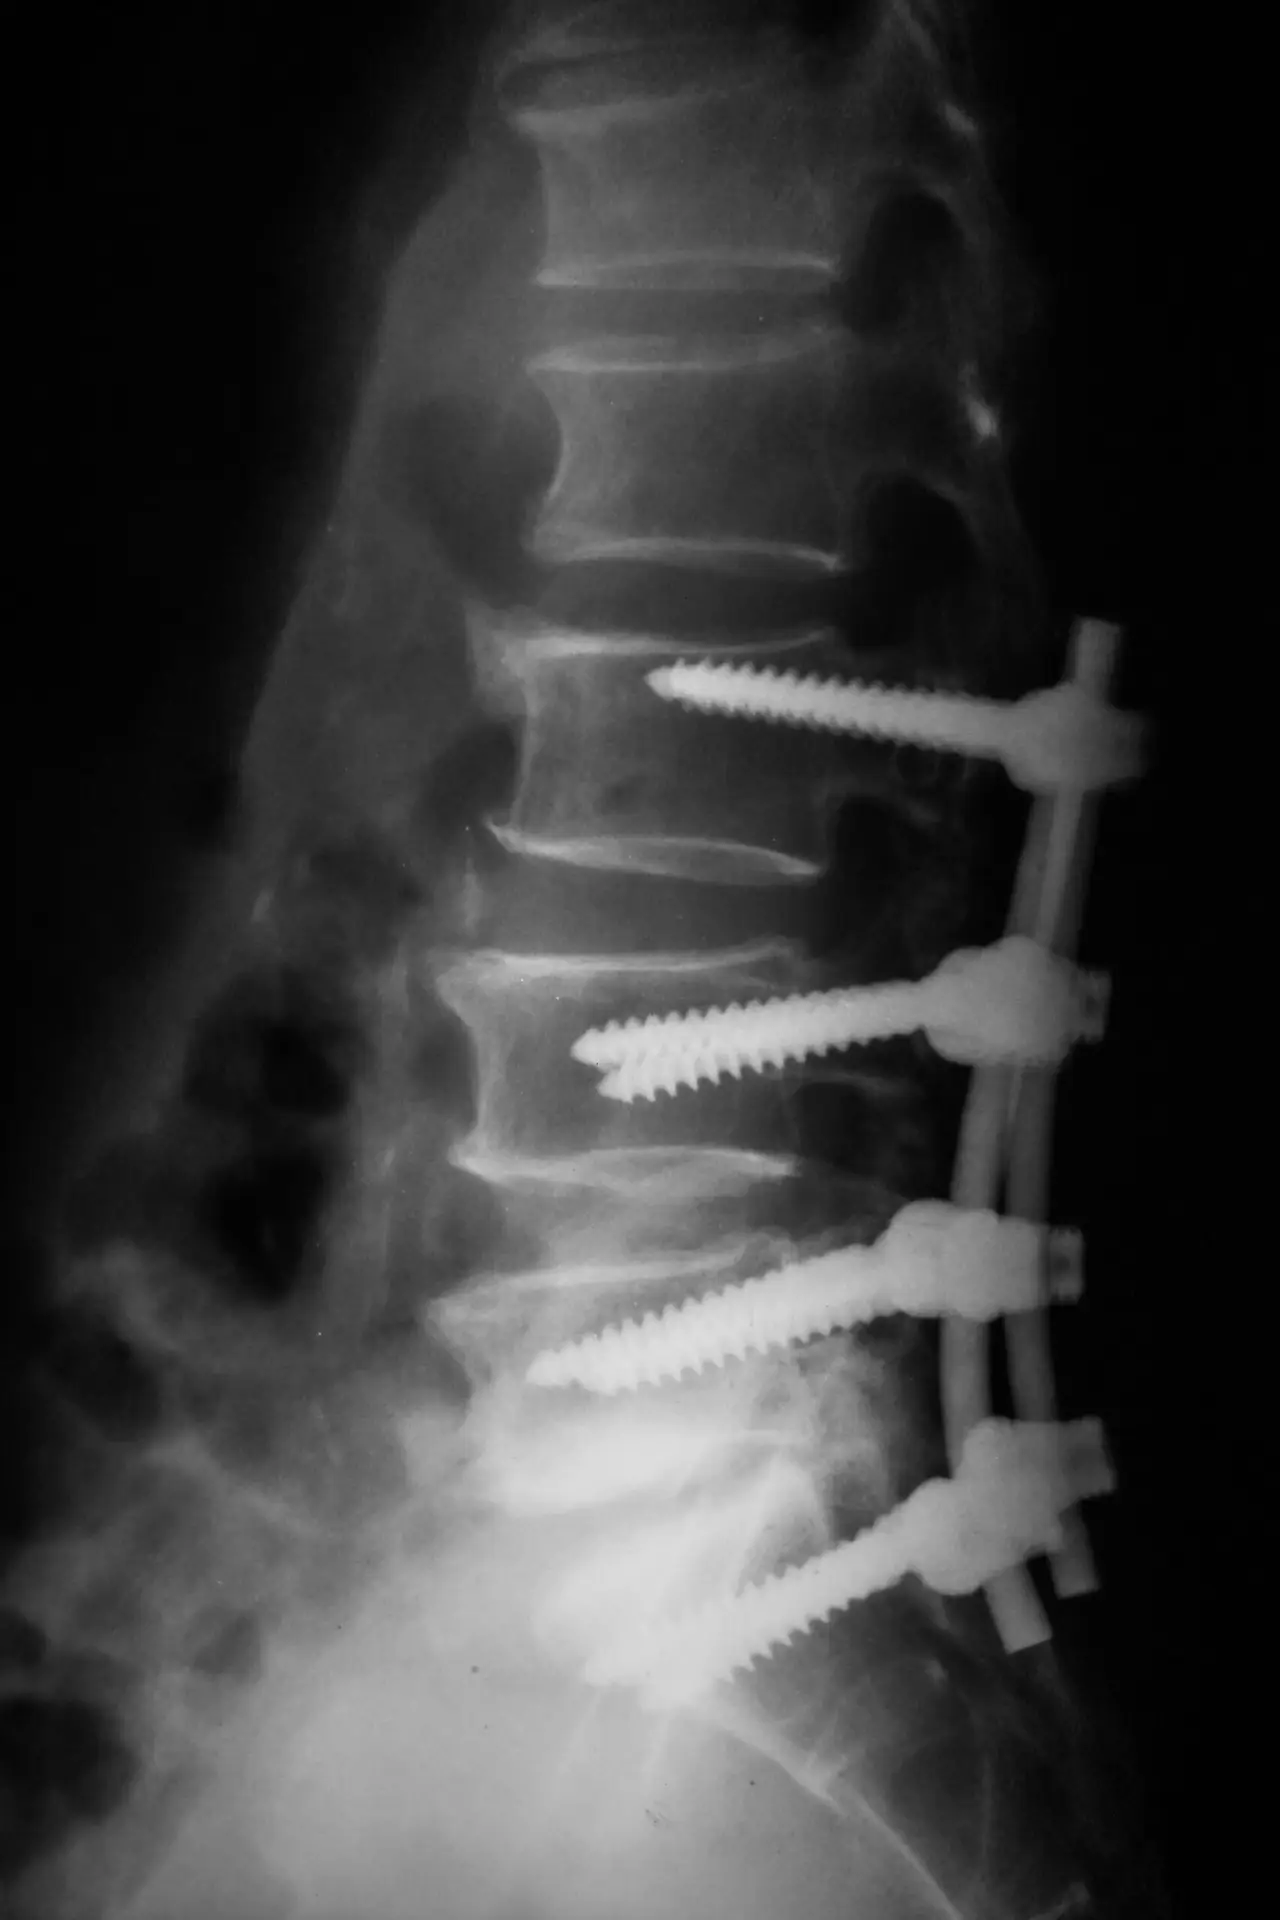

an x-ray image of a lower back with pins and screws in the vertebrae

Imaging tests including X-rays, CT scans, and MRI scans are used to diagnose fractures of the spine. The results will help your medical team determine the best course of treatment for you. Some options for treatment are:

Spinal Surgery

More severe broken-back injuries require surgical intervention. Spinal surgery attempts to return the bones to their natural position, stabilize the fracture, relieve pressure on the spinal cord and nerves, and allow for normal movement. When you have other life-threatening conditions due to an accident or assault, spinal surgery will be delayed until those injuries are stabilized.